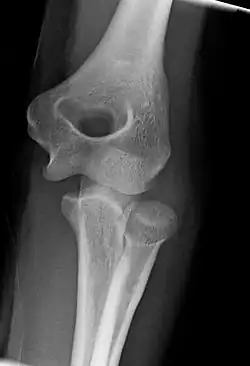

The elbow undergoes dynamic development of ossification centers through infancy and adolescence, with the order of both the appearance and fusion of the apophyseal growth centers being crucial in assessment of the pediatric elbow on radiograph, in order to distinguish a traumatic fracture or apophyseal separation from normal development. The order of appearance can be understood by the mnemonic CRITOE, referring to the capitellum, radial head, internal epicondyle, trochlea, olecranon, and external epicondyle at ages 1, 3, 5, 7, 9 and 11 years. These apophyseal centers then fuse during adolescence, with the internal epicondyle and olecranon fusing last. The ages of fusion are more variable than ossification, but normally occur at 13, 15, 17, 13, 16 and 13 years, respectively.[16] In addition, the presence of a joint effusion can be inferenced by the presence of the fat pad sign, a structure that is normally physiologically present, but pathologic when elevated by fluid, and always pathologic when posterior.[17]

Right: AP X ray of a dislocated right elbow

There are three bones at the elbow joint, and any combination of these bones may be involved in a fracture of the elbow. Patients who are able to fully extend their arm at the elbow are unlikely to have a fracture (98% certainty) and an X-ray is not required as long as an olecranon fracture is ruled out.[27] Acute fractures may not be easily visible on X-ray.[28]